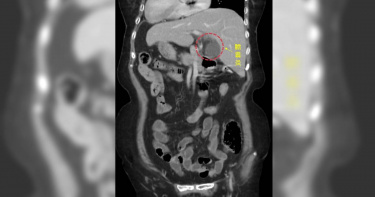

一位80歲左右的阿嬤,因左上腹痛來中國醫藥大學新竹附設醫院急診,左上腹痛一般應是胃痛或大腸發炎,做了電腦斷層發現阿嬤是一個「鏡面人」,所謂「鏡面人」就是他的內臟等器官跟一般人的位置顛倒,經過一般外科古君平醫師診斷,阿嬤是急性膽囊炎。「鏡面人」左右顛倒的內臟是外科手術挑戰,古君平醫師首次遇到,一般膽囊手術需約半小時即可完成,這次手術花了一個半小時才完成,透過腹腔鏡微創手術,順利切除膽囊,術後兩天就順利出院。古君平醫師表示,所謂的「鏡面人」包括腹腔、胸腔內器官的位置與一般人剛好相反,例如一般人心臟脾臟在左邊,肝臟位於右邊,鏡面人心臟脾臟在右邊,肝臟在左邊,就好像正常人的鏡中影像,故出現「鏡面人」的稱呼。這是一個罕見的遺傳病,發生率大約是萬分之一左右,不過內臟功能跟一般沒什麼差別,所以只要沒有生病沒做檢查,一般人不會知道自己的內臟跟別人的位置不一樣,這次阿嬤因為急性腹痛做電腦斷層,才發現他的內臟跟一般人相反。古君平醫師表示,所謂的「鏡面人」包括腹腔、胸腔內器官的位置與一般人剛好相反。(圖/中醫大新竹附設醫院提供)因為鏡面人的特殊性,醫師診斷需特別小心,否則可能把病患左上腹痛當成是胃痛治療,實際上膽囊炎,發生誤診,尤其在施以手術時,與醫生的熟悉手勢有所不同而增加難度。膽囊切除是一個很常見的手術,膽囊功能儲存膽汁,膽汁是肝臟製造,所以膽囊切除之後,肝臟還是會正常分泌製造膽汁,因此,阿嬤切除膽囊,對她的生活並不會有太大影響。大部分的人可能在術後一個月左右會有容易拉肚子的情形,不過,等肝臟適應這種情況後,就可以恢復正常生活。古君平醫師指出,膽囊結石或膽囊炎是一個膽囊結石的情況,,膽囊結石如果塞住,膽汁分泌不出來就會腹痛,膽結石最常出現在臨床上,有四個好發族群,我們稱之4F,第一個F(Female)女性,第二個F(Fat)肥胖的人,再來就是年紀Forty第三個F四十歲,最後一個F是多產婦(Fertile),因此,四十歲左右肥胖的多產婦女可能比較容易有膽結石。會建議有這樣風險的族群,少油膩少油炸,三餐盡量正常讓膽汁、膽囊順利工作,比較不會有膽汁淤積或膽結石的風險。